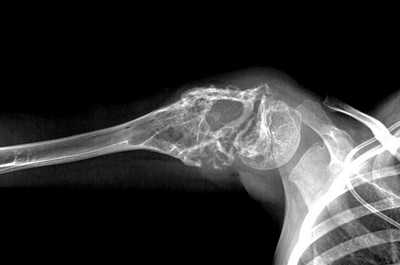

— Рентгенологическое исследование. Позволяет визуализировать тень опухоли, деформацию прилежащих к опухоли фасциальных перемычек, выявить изменения в костях;

- рентгенография пораженного сегмента скелета в 2-х стандартных проекциях;

Рентгенологические признаки саркомы Юинга:

- поражение кости без четких границ, так называемый симптом «изъеденная молью», чаще распространяется по костномозговому каналу;

- «луковичный периостит» - многослойный периостит, сочетающийся с игольчатым;

- наличие мягкотканного компонента однородной структуры;

- в 5% случаев встречается патологический перелом.

Саркома Юинга плечевой кости